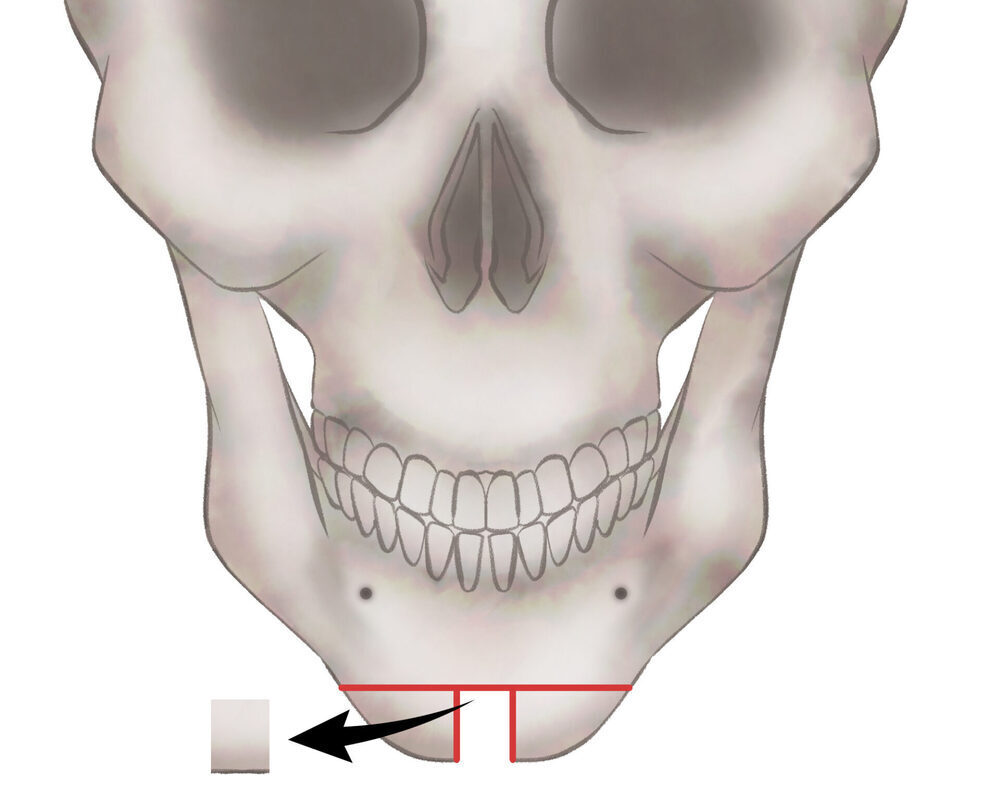

オトガイ骨切り(中抜き)

1.切開線をデザインします

2.骨を切除します

3.骨を移動させ段差を削ります

4.プレートで固定します